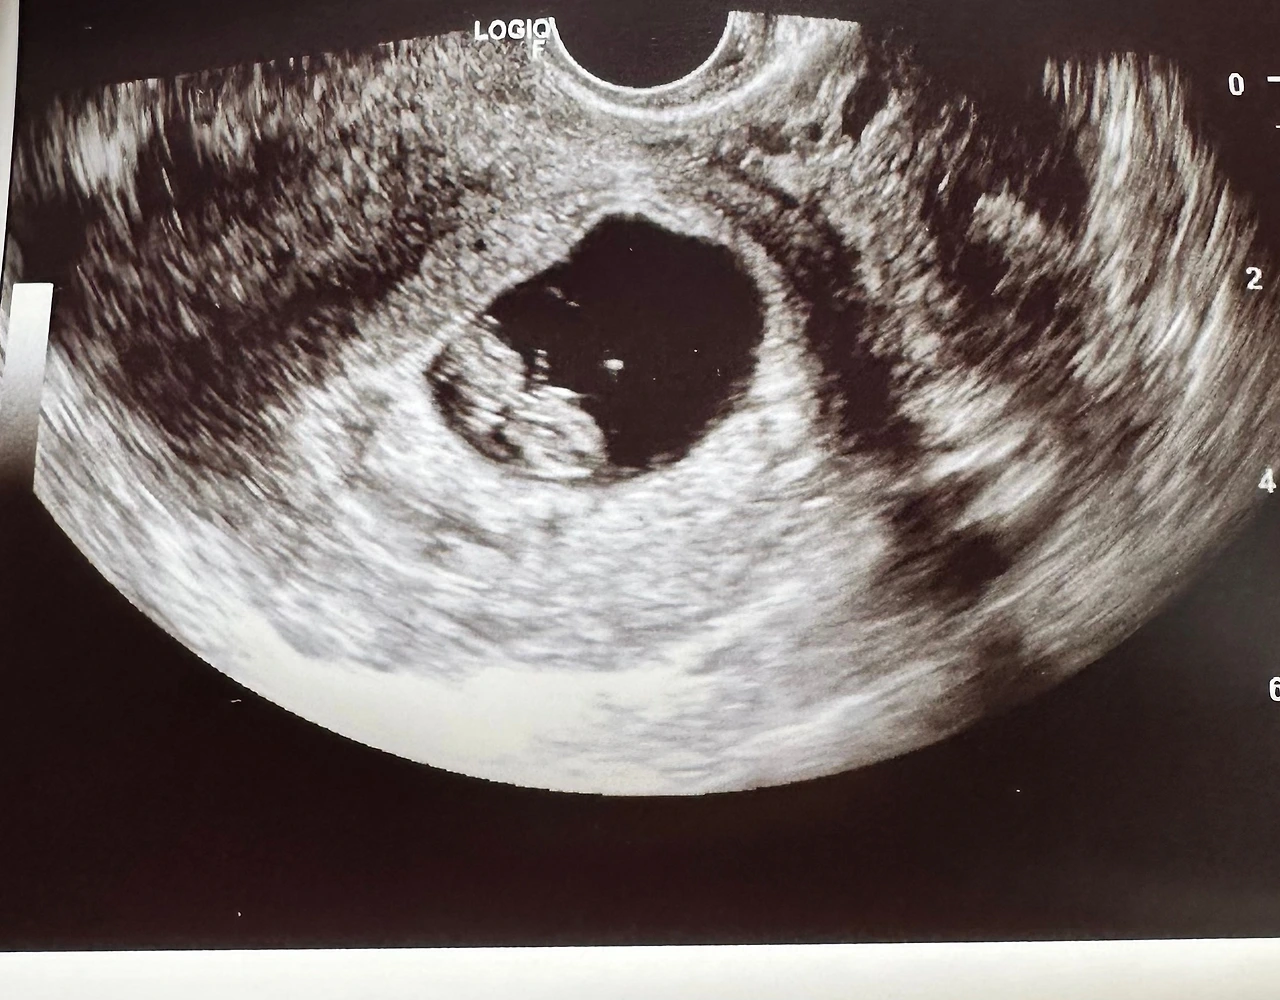

아내는 미국에서 초음파를 찍었다.

아내는 초음파 사진을 비춰주며 조심스레 웃었다.

화면 속의 작은 점 하나가,

규칙적으로, 또렷하게 뛰고 있었다.

그건 수치도, 통계도 아니었다.

그건 살아 있는 생명의 박동이었다.